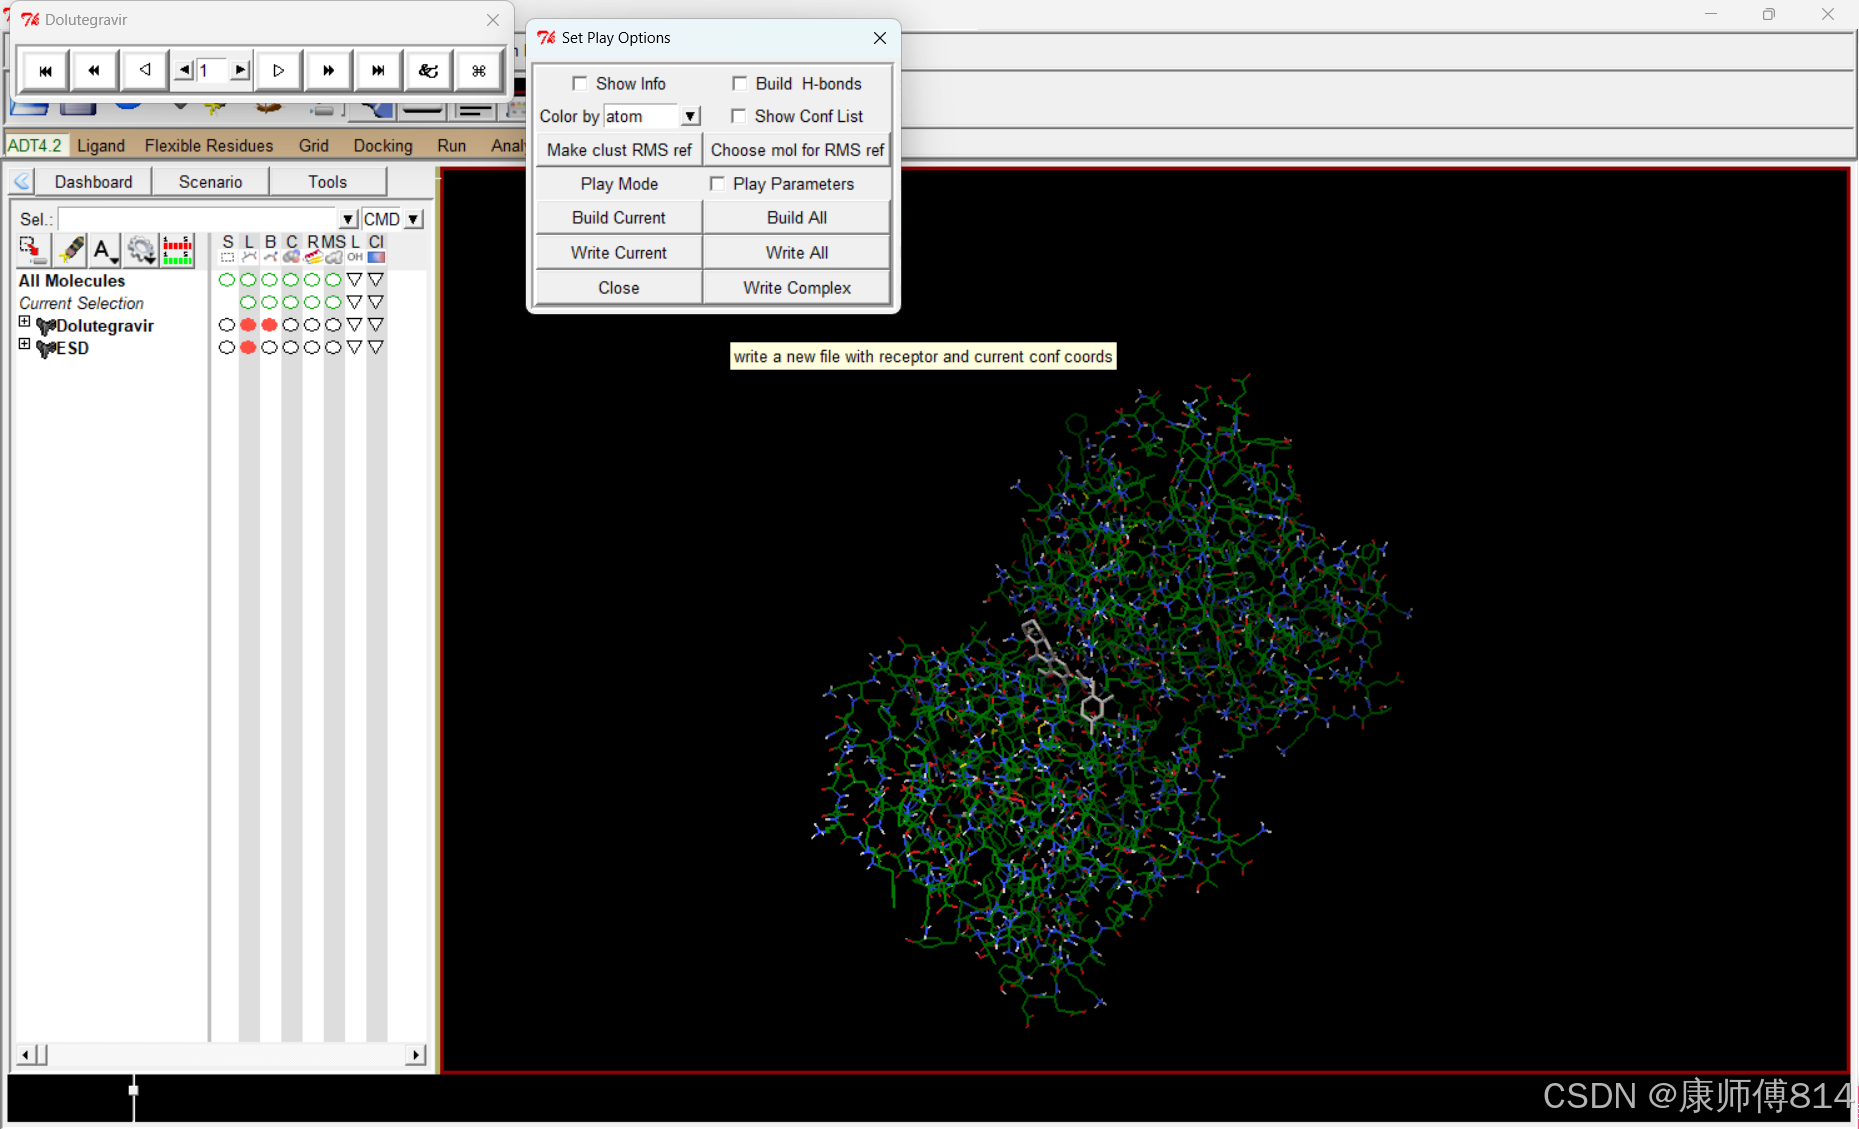

#对接完成后,查看对接结果

#删去所有分子,点击Edit-Delete-Delete All Molecules

#点击Analyze-Dockings-Open,打开后缀为.dlg的结果文件

#点击Analyze-Macromolecule-Open打开分子结构

#点击Analyze-Conformations-Play ranked bu enegy,可按照结合自由能从最小到最大顺序观看结合状态(默认模拟对接10次)

#另外,直接用记事本打开.dlg文件也可以直接看到所有对接结果的结合自由能

导出对接结果

#点击Set Play Options-Whie Complex导出选中的对接状态为pdbqt文件,这里我导出为ESD-Dolutegravir.pdbqt